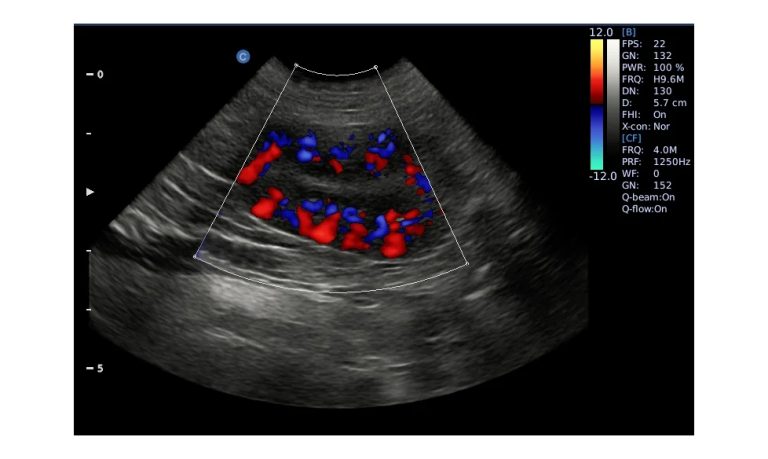

EBIT50/60 VET

All the power you need

The EBit provides all the power you need for today´s challenging clinical environment, yet remain ultra-portable, ultra-affordable. With its cutting-edge imaging technologies, precise and intuitive workflow, ergonomic and eco-friendly design, versatile transducers for all applications from top to toe, we firmly believe the EBit to be the very best portable ultrasound in its class today.